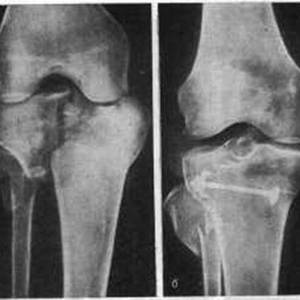

Опытный специалист может определить перелом мыщелка бедренной кости уже по основным признакам и после пальпации. Но так как травма обычно бывает сочетанной, то для уточнения применяется дополнительная диагностика.

Это позволяет увидеть наличие трещины, перелома, степени смещения мыщелков с деформацией, а также возможные нарушения других структур и тканей в области коленного сустава.

При вдавленном переломе используется снимок суставной площадки. Для определения протяженности перелома назначаются снимки в косой проекции.

Обычно проведения рентгеновской диагностики бывает достаточно для уточнения диагноза. Если по какой-то причине ее результаты не устраивают специалиста, то более точную картину патологии можно получить с помощью КТ или МРТ. Эти исследования помогают диагностировать скрытые формы переломов и разрывы связок.

Если перелом проходит через оба мыщелка, то такое отклонение называется чрезмыщелковым переломом. Компрессионная форма (сдавление) выглядит при исследовании неровной линией с множественными обломками. Импрессионный перелом латерального мыщелка большеберцовой кости или медиального, который переводится как «вдавленный» может сочетаться с компрессионным.